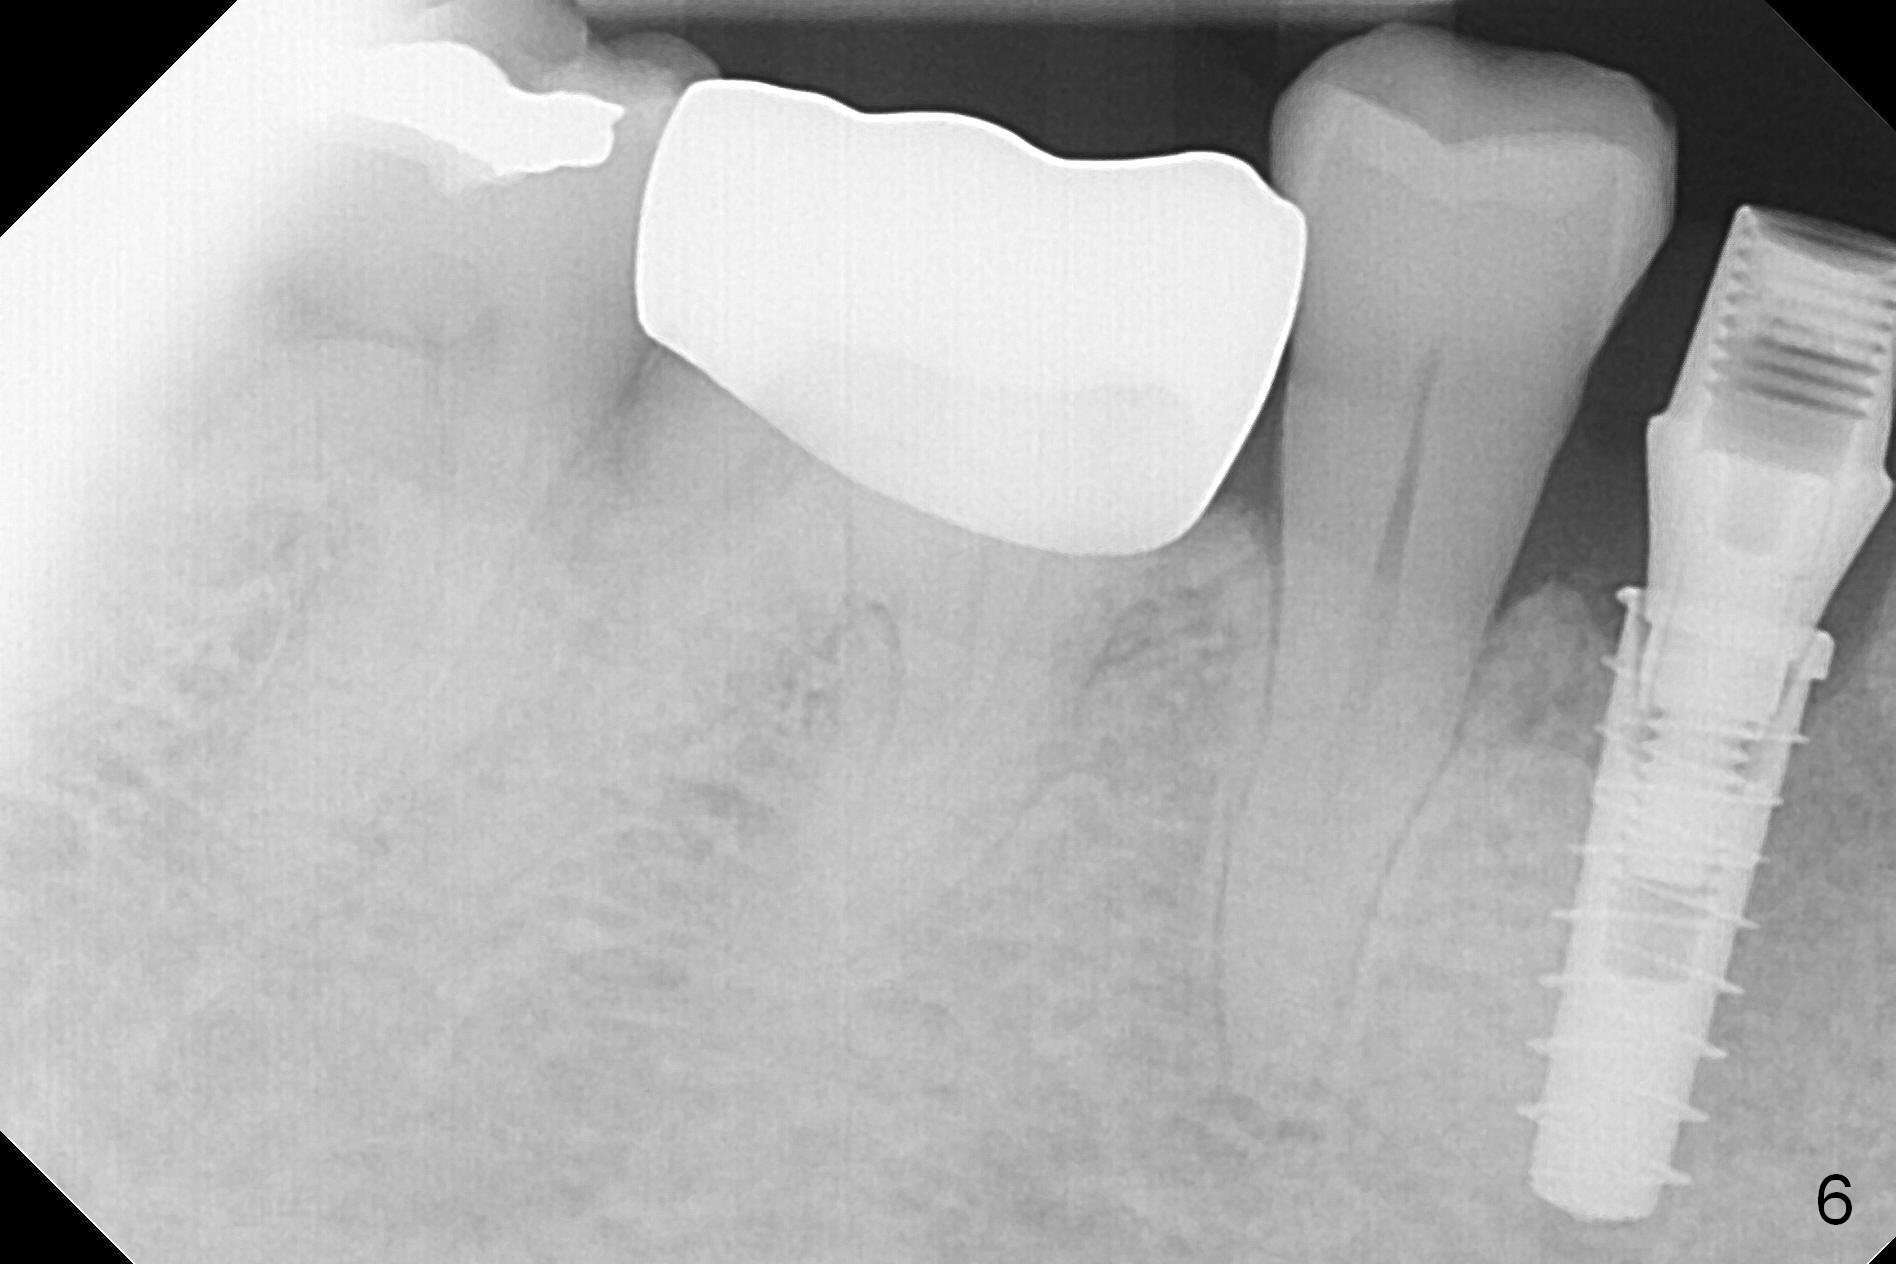

In fact the mesiodistal space of the site of #28 is within normal limit. The buccal plate atrophy is striking (Fig.1) with a fistula (^, associated with underlying residual root tip). When the flaps are raised, the ridge is triangular with the lingual plate (Fig.2 *) higher than the buccal one. Because of the slope, the multiple-drill approach is adopted in stead of single-drill one, because the marking bur is wobbling after 1.6 mm osteotomy at 13 mm (Fig.3). After placement of a 4x11 mm implant, a 4.5x4(2) mm abutment is inserted (Fig.4). The abutment and the implant act as a mesh (framework) so that bone graft and collagen membrane can be laid upon them buccolingually. When the flaps are sutured, there is less tension than that without the abutment. Furthermore, the buccal tissue volume seems to be increased (Fig.5 (<: fistula, which should heal soon), as compared to Fig.1). Tale photos to show effectiveness of the simultaneous GBR and disappearance of the fistula. Three months postop (Fig.6,7 (incomplete abutment seating)), the implant is loaded for intrusion of the opposing supraerupted tooth. The patient returns with chief complaint of food impaction between #27 and 28 three years 7 months post cementation; there is an open contact. Before pick up impression the distal convex surface of #27 is trimmed. The repaired crown has tight proximal contacts before (Fig.9,10) and after (Fig.11) retightening and cementation.